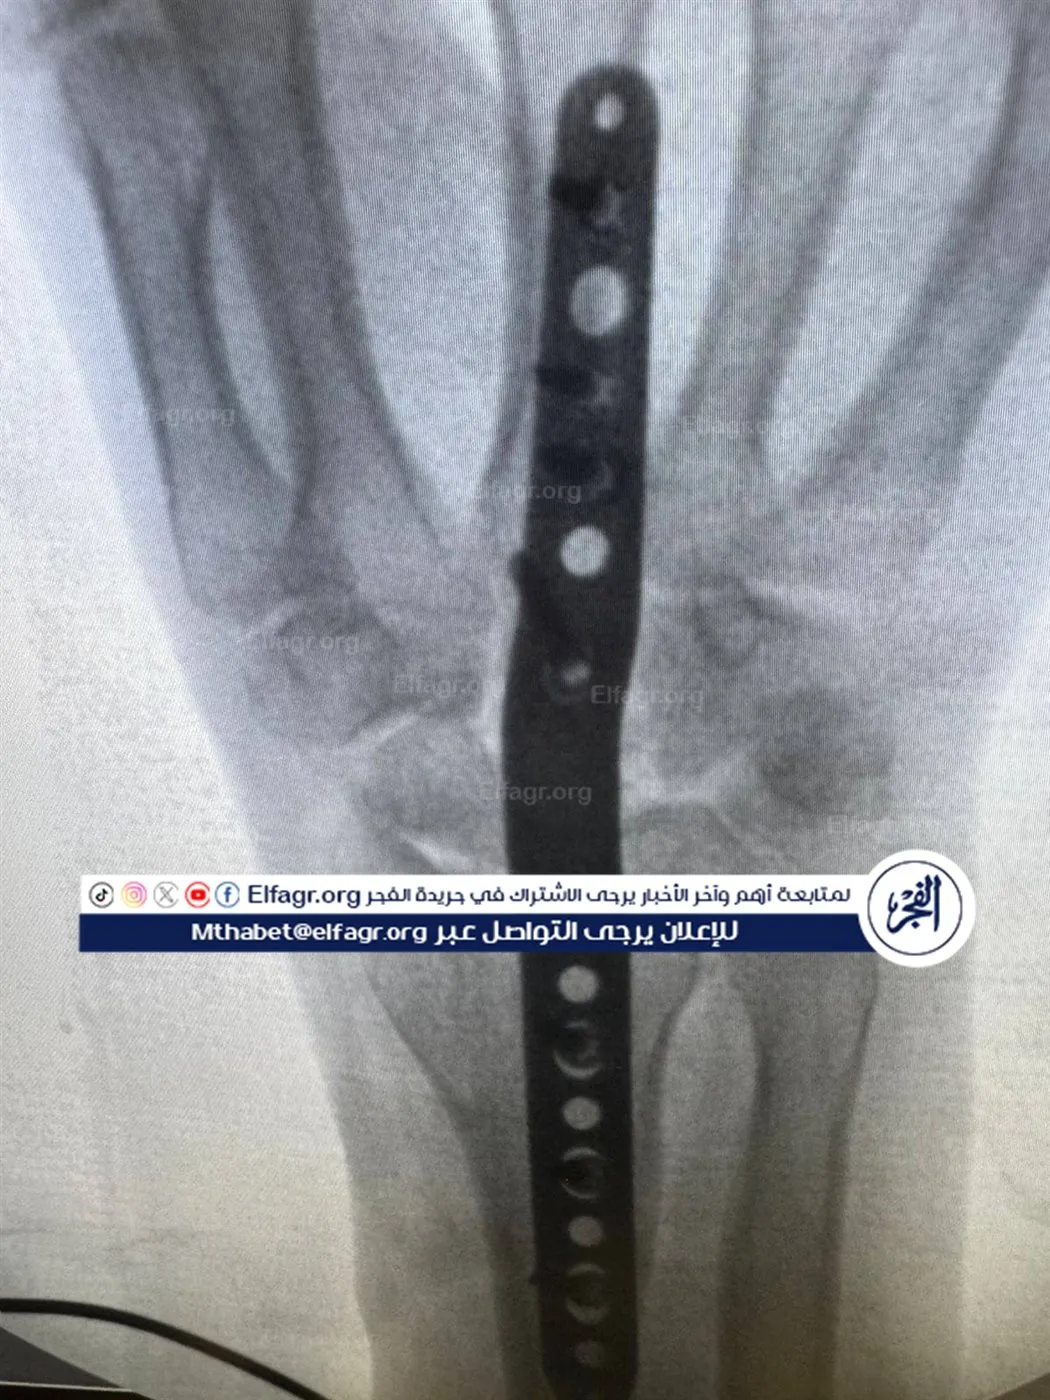

يشير فارس إلى أنه كان متفقًا مع النادي على إجراء العملية باستخدام المنظار، إلا أنه فوجئ بإجرائها جراحيًا في أحد المستشفيات بالقاهرة بتاريخ 5 فبراير 2024، قائلا: اتفقت معاهم إنها هتتعامل بالمنظار، لكن لقيتها اتعملت جراحة مفتوحة.. قالوا لي هتبقى زي الفل، لكن بعد ما فكت الجبس اكتشفت إن إيدي محتاجة عمليات تانية.

ويؤكد اللاعب أنه خضع لاحقًا لعمليتين إضافيتين على نفقته الخاصة، بعدما تدهورت حالته وأصيب بعجز في حركة اليد، قائلا: مبقاش في أي حركة وحياتي الكروية انتهت، وتصاعد الأزمة تصاعدت عندما عاد إلى النادي لمتابعة حالته، ليُفاجأ بقرار فسخ التعاقد دون إخطاره رسميًا، قائلا: العقد بتاعي ساري لحد 2027، ومفيهوش بند يسمح بفسخه من طرف واحد وفجأة قالوا لي ملكش حاجة عندنا، كما أكد أن النادي لم يقم بتحرير وثيقة تأمين خاصة بإصابته، رغم كونها إصابة عمل حدثت أثناء التدريب.